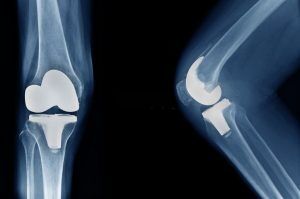

Knee Replacement Surgery

The largest joint in the body, the knee joint is formed where the lower part of the thighbone (femur) joins the upper part of the shinbone (tibia) and the kneecap (patella). Shock-absorbing cartilage covers the surfaces where these three bones touch.

In a standard total knee replacement, the damaged areas of the thighbone, shinbone and kneecap are removed and replaced with prostheses. The ends of the remaining bones are smoothed and reshaped to accommodate the prostheses. Pieces of the artificial knee are typically held in place with bone cement.

Most who opt for knee joint replacement are generally happy with the results. Ninety percent of those who have total knee replacement report fast pain relief, improved mobility, and better quality of life, according to a panel of independent experts.Dr Hardik Shah, senior orthopaedic surgeon and joint replacement surgeon at shreeji hospital, gurukul road, ahmedabad provides all joint replacement surgery like TKR, THR knee and hip replacement accurately with best long term results, without post-op physiotherapy near gurukul road, memnagar, ghatlodiya, vastrapur, satellite, thaltej, hebatpur, shilaj, naranpura, navrangpura, satellite in Ahmedabad.